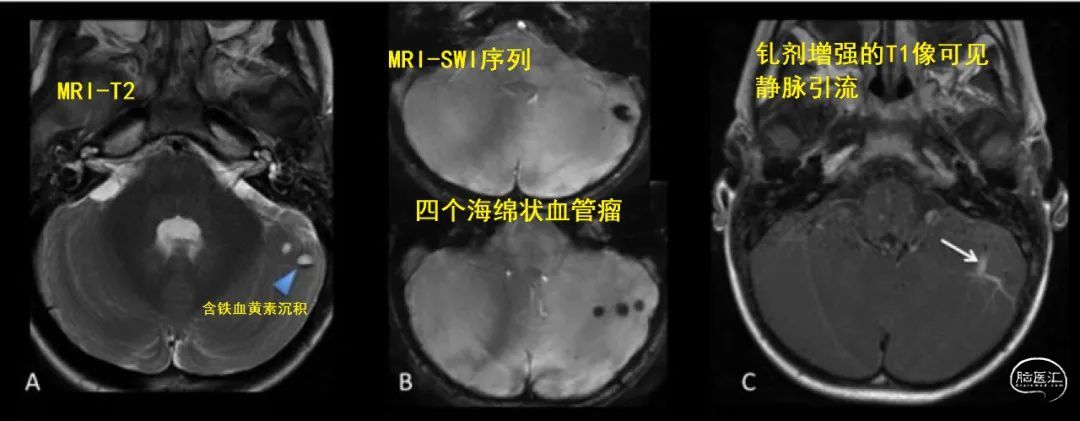

30岁以下脑干出血挺少见的,得高度怀疑是不是血管出了问题;例如有没有并发海绵状血管瘤,或者发育性静脉畸形?

复查核磁超级重要,这事儿可不能马虎。就算康复得再好,定期去看看医生也是必须的;随访核磁检查能发现的、那些藏着的血管畸形,对预防再出血有大帮助。

③要是发现血管畸形,得赶紧评估一下,看看要不要治疗,看图: